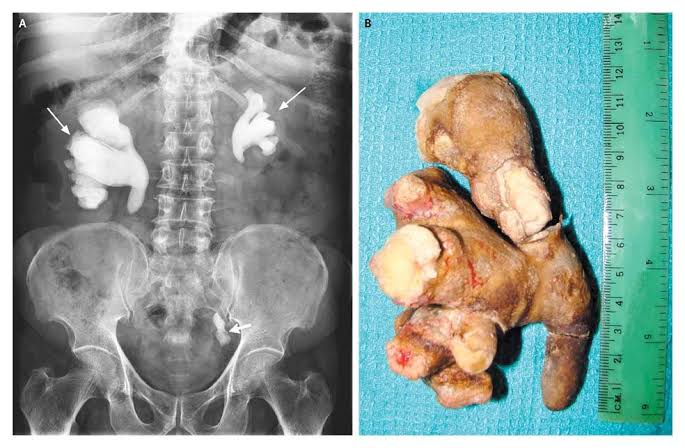

しょうが?

でけえ

これが尿道から出てくるとか地獄かよ

もうショウガにしか見えない